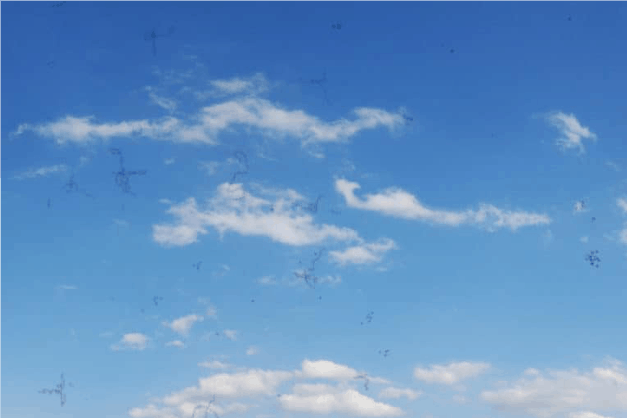

Floaters –Small specks, dots, circles, lines or cobwebs

- The vitreous gel shrinks and also changes from being gel-like to being more watery and stringy over time.This causes the formation of strands which cast tiny shadow on the retina which we see as floaters.